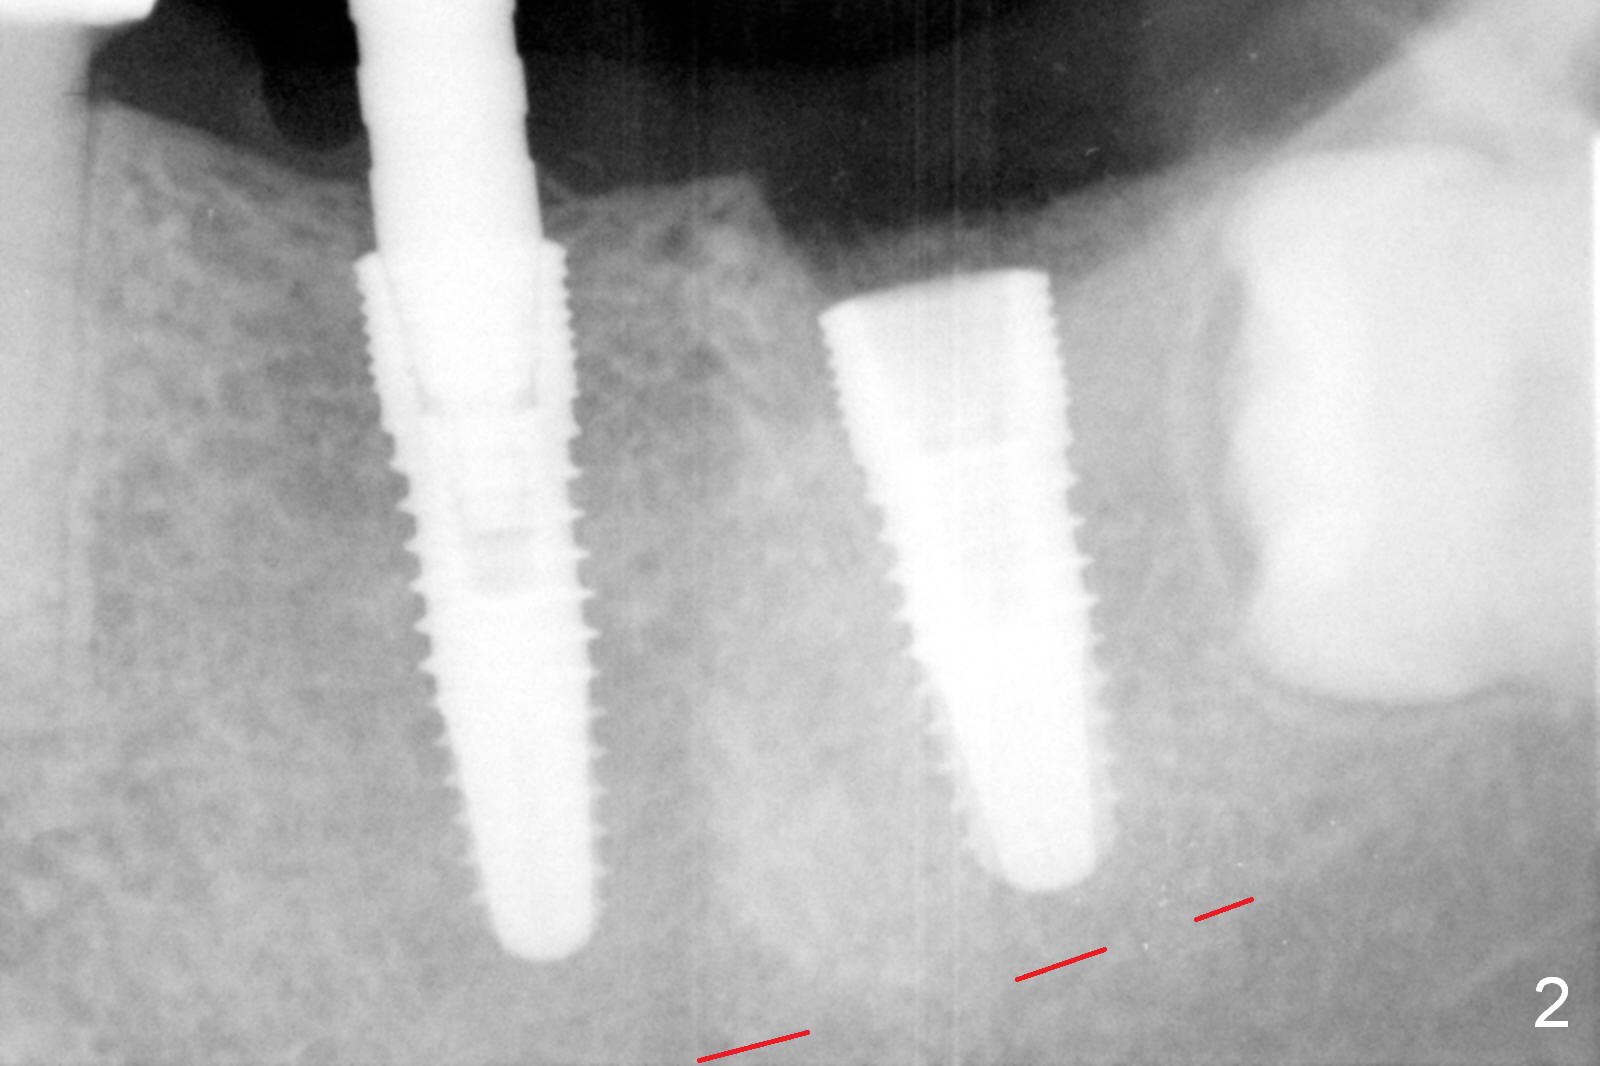

Infiltration anesthesia is enough for initial osteotomy at the site of #19 (Fig.1), but not for sectioning the tooth #18.  Block anesthesia has to be administered.  Fortunately it is safe to start osteotomy at #18 (~ 3 mm beyond the socket bottom, Fig.1 (red dashed line: the superior border of the Inferior Alveolar Canal (IAC))).  A 4.5x14 mm implant is stable at #19, while a 5x12 mm one at #18 is not (Fig.2).  Unfortunately bone graft has been placed.  When the implant is removed, a 4.5x14 mm drill is used to deepen the osteotomy for 2 mm.  The patient reports mild discomfort later on.  Hemorrhage occurs, which is stopped when the same implant is re-placed.  There is no stability.  The implant is removed (Fig.3,4).  More bone graft is placed, followed by collagen plug.  It appears that bone graft has been pushed into the IAC (Fig.4 arrowheads). Medro dose pak is prescribed.  In fact, no paresthesia is reported postop.